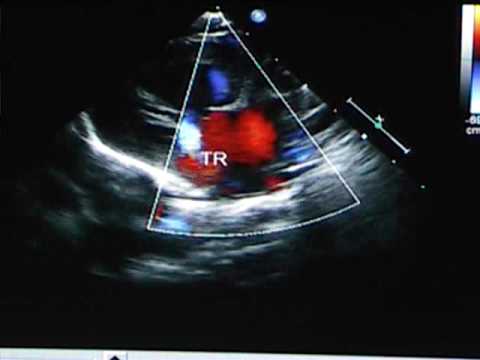

Echocardiogram

One of the common tests used for diagnosing HLHS, it produces a detailed image of the patient’s heart using an ultrasound or echocardiogram sound waves. The process can also be used to diagnose the disorder in an unborn child.

Picture 2 – Hypoplastic Left Heart Syndrome Image